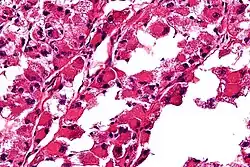

| Micrograph of an alveolar soft part sarcoma, showing the characteristic alveolar-like architecture and cells with eccentric nuclei and abundant eosinophilic cytoplasm. H&E stain. | |

- The term alveolar comes from the microscopic pattern, visible during the analysis of slides of ASPS under the microscope in histopathology. The tumor cells seem to be arranged in the same pattern as the cells of the small air sacks (alveoli) in the lungs. However, this is just a structural similarity. ASPS was first described and characterized in 1952.[1]

The definitive diagnosis of ASPS is based on its appearance under the microscope (i.e., its histomorphology), and presence of the characteristic chromosomal translocation (i.e., cytogenetics).

ASPS' histomorphologic features include an alveolar-like pattern at low magnification and the presence of large cells with abundant eosinophilic cytoplasm and eccentric nuclei. Calcifications are commonly present, as may be seen with slow-growing neoplasms.